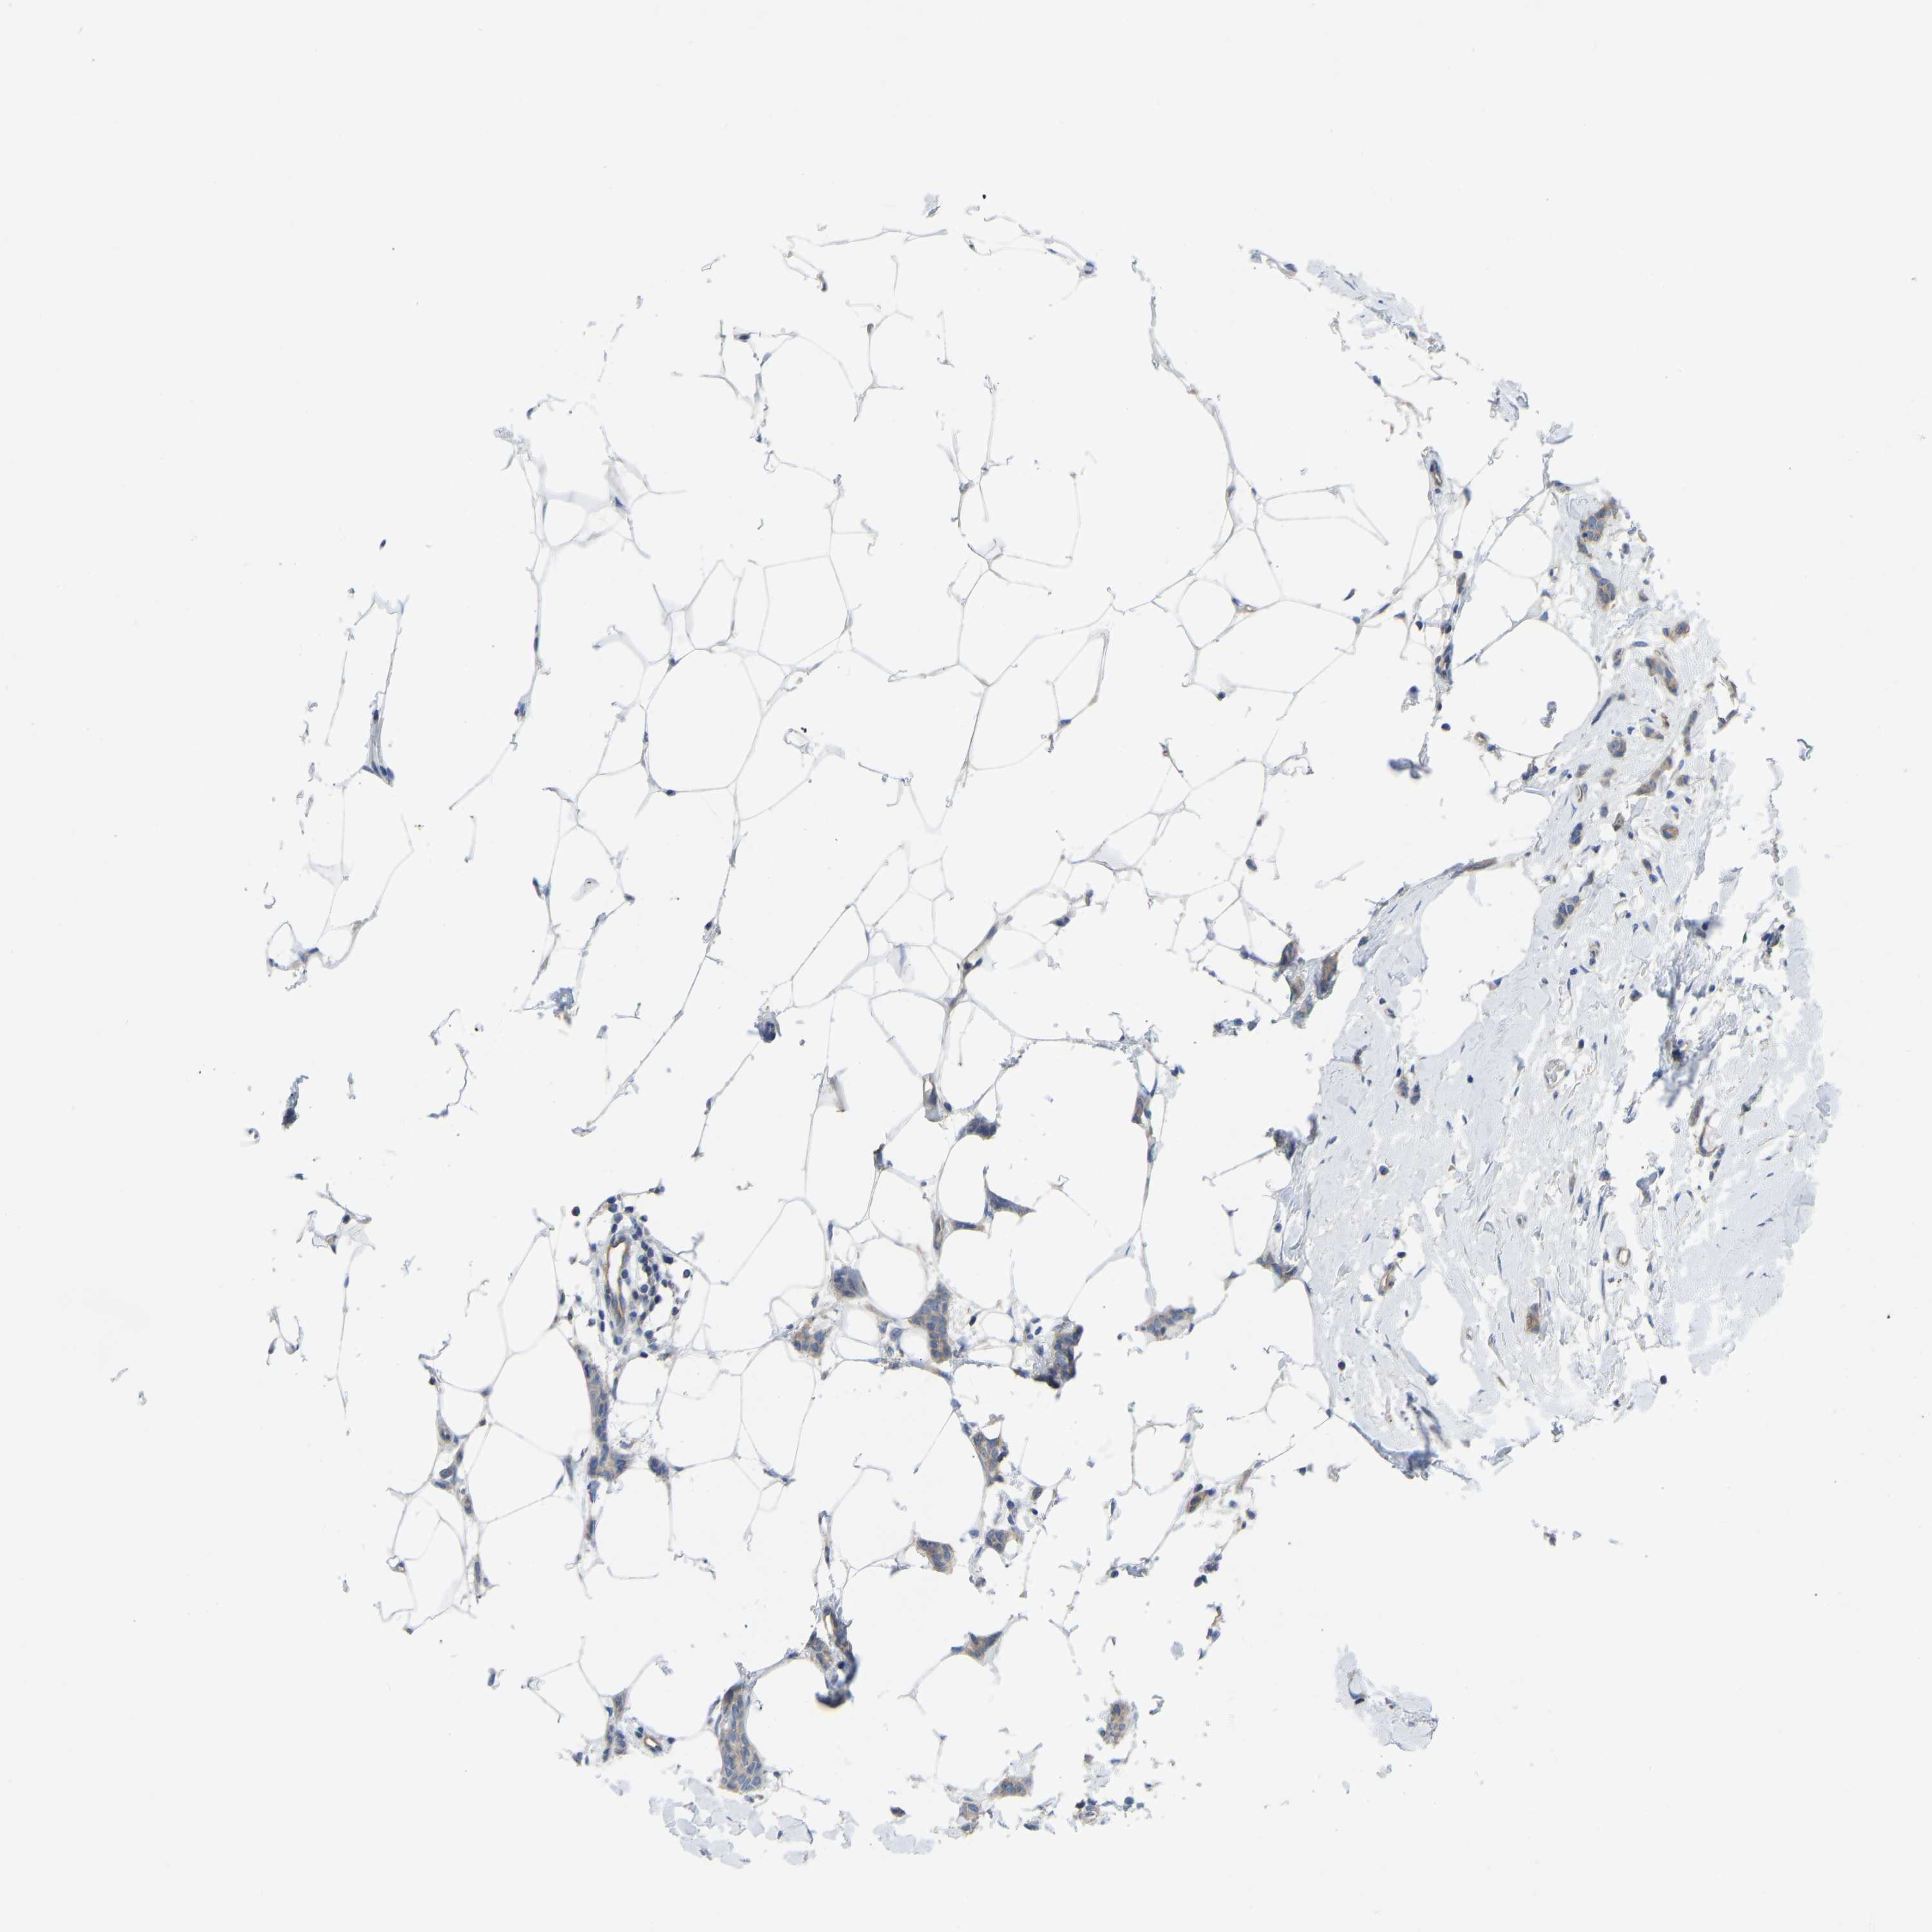

CANCER BREAST CANCER Show tissue menu

BRCA TCGA BRCA VALIDATION PROTEIN EXPRESSION

Breast cancer

Human cancer